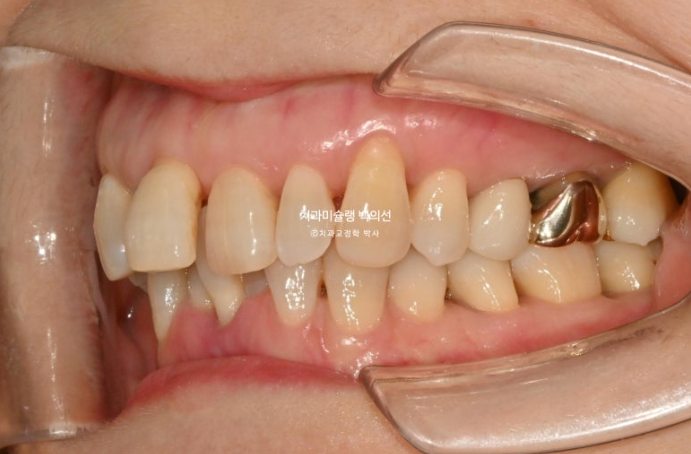

1년 전 치아 틀어짐이 점점 심해지면서 찾아오신 50대 환자분

예전에는 입이 편하게 다물어졌었는데 치아가 틀어지고 벌어지고 내려오면서 이제는 입이 편하게 안 다물어지는 것도 불편한 상태입니다.

위 앞니는 잇몸이 꽉 잡아주지를 못해서 점점 솟아 내려오고 튀어나오면서 치아사이가 벌어졌습니다.

작은어금니도 안으로 쓰러져 있어서 이 부분은 윗니와 엇갈려 물리는 가위교합 입니다.